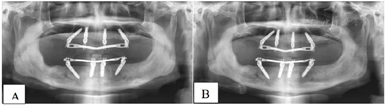

(5)术后复查:术后1个月、5个月复诊,上下颌过渡义齿咀嚼功能较戴用可摘义齿明显改善,面型及发音正常。X线全颌曲面体层片显示种植体骨结合良好(图10)。

种植修复后1、2、4年随访X线全颌曲面体层片显示种植体周围骨结合良好(图13A~C),患者对修复体美观及咀嚼功能效果满意。修复后6年(2022年8月)随访X线全颌曲面体层片及根尖片显示种植体周骨结合良好,上前牙区种植体颈部骨吸收约1 mm(图13D、图14)。取下上下颌义齿,清理义齿组织面滞留菌斑,清洁复合基台并检查基台中央螺丝稳定,清洁义齿组织面,戴回上下颌义齿(图15)。患者口腔卫生宣教,指导正确刷牙,使用冲牙器冲洗义齿与牙龈间缝隙,嘱6个月复查、维护。